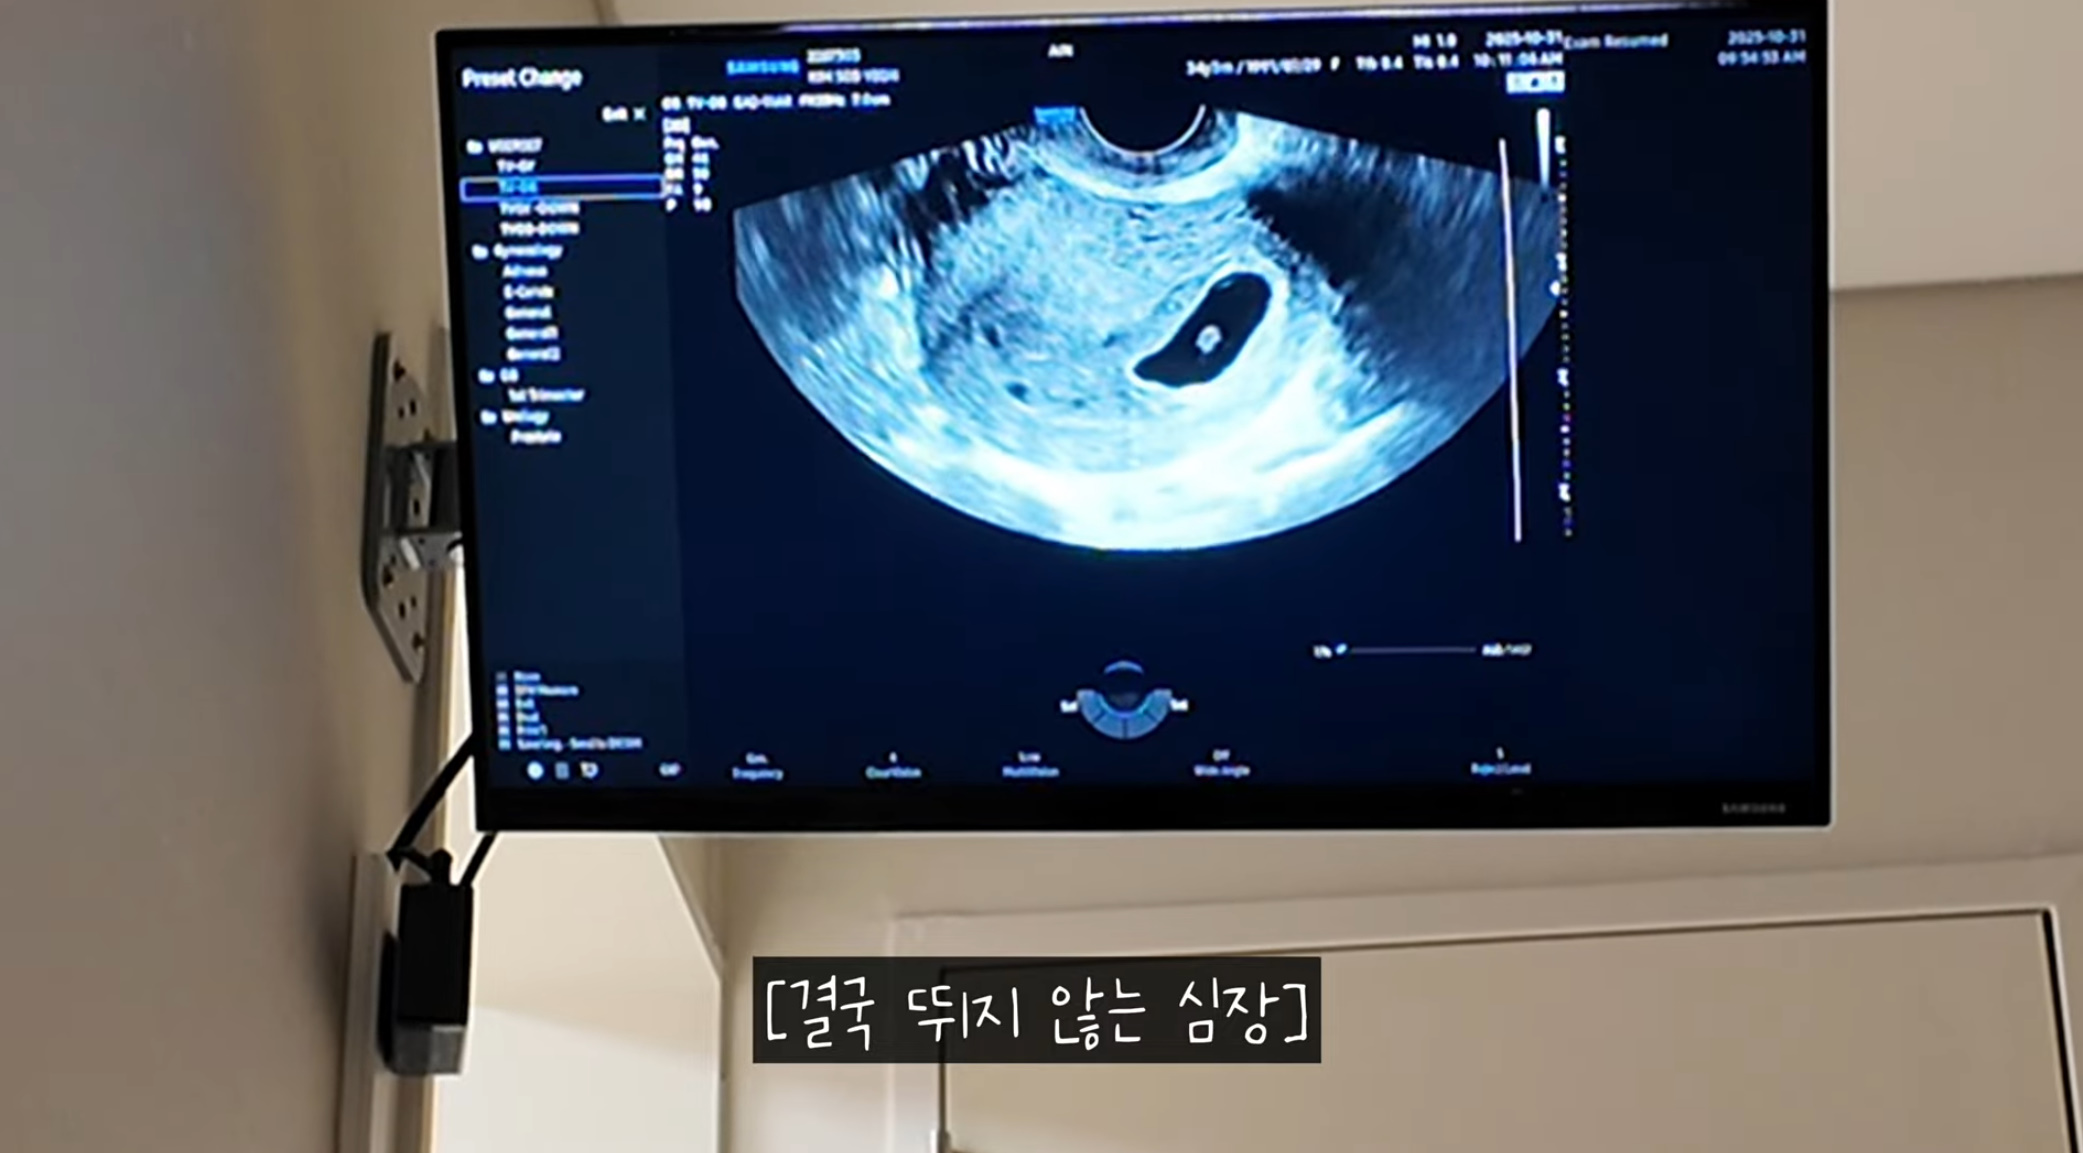

1일 유튜브 채널 '로부부'에는 '기적의 심장깜빡임 | 그리고 진짜 안녕 | 로부부 임신일기 마지막'이라는 제목의 영상이 올라왔다.

의사는 "정상적으로 임신이 진행될 가능성은 1~2% 미만일 것 같다. 하지만 기다려 봐야겠죠? 괜히 희망 고문만 하다가 마는 경우가 워낙 많아서 일반적인 코스에서는 진행되긴 어렵다고 봐야한다. 심장 소리는 안 들리는데 깜빡거리는 게 보인다"라고 진단했다.

두 사람은 상의 끝에 3일 더 기다려보기로 했다. 3일 뒤에 다시 검사했지만 배아의 심장은 뛰지 않았다. 의사는 "다음 임신을 위해서"라며 "이런 걸 계류유산이라고 한다. 계류유산이라는 의미는 유산이 됐는데 남아있다는 뜻이다. 만들어지고 있었는데 문제가 생겨 진행이 안 되는 상황이다. 보통 7~10% 안쪽에서 늘상 발생한다"라고 설명했다.